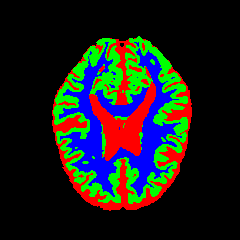

• OASIS-1 [34]: Derived from the Open Access Series of Imaging Studies, this dataset comprises T1-weighted MRI scans from 421 subjects (aged 18–96). The images were acquired with a resolution of 176×208176\times 208 pixels and a slice thickness of 1.25 mm (TR=9.79.7 ms, TE=4.04.0 ms, TI=2020 ms). Following standard protocols, we utilize the provided manual segmentation masks for Cerebrospinal Fluid (CSF), Grey Matter (GM), and White Matter (WM).

7 Qualitative Evaluation

Fig. 8 and Fig. 10 provide qualitative comparisons on the OASIS-1 and MRBrainS13 datasets, respectively. It is visually evident that the baseline predictions (c) and standard augmentations (e.g., (d), (g), (i)) frequently suffer from noisy artifacts, blurred boundaries, and mis-segmentation of intricate anatomical structures. In stark contrast, our ”Ours+” enhanced methods (e.g., (e), (h), (k)) consistently produce segmentation maps that are visibly cleaner, more spatially coherent, and demonstrate significantly sharper adherence to the Ground Truth (b). This superior fidelity is particularly noticeable in the complex sulcal patterns and holds true across all three backbones (rows), confirming that our framework yields more robust and anatomically plausible results.